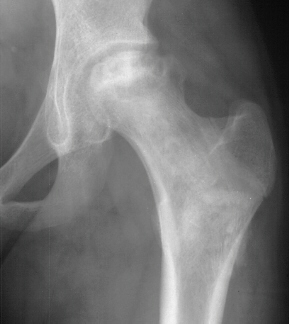

M.L. was diagnosed as having sickle cell anemia during early childhood.

She experienced two major crises each year, treated with hydration and

pain medication. She was first seen at age 9 following a crises with concomitant

left hip pain

Bone scan was also obtained which demonstrated a cold area. Treatment consisted

of activity restriction and partial wt. bearing.

F/U age 14 with a 2mo. history of left hip pain, aggravated with activity.

Clinical findings were not suggestive of infection. She was diagnosed with

AVN of the left femoral head. Management consisted of NSAIDS, restricted

wt. bearing.

Two months later she under went a left hip core decompression and bone

grafting without problem

Rehabilitation was steady maintaining a restriction on wt. bearing and

encouraging range of motion. She had a significant decrease in her pain

although the radiographs showed progressive collapse.

Four years later, she is able to ambulate without any aids but complains

of a dull ache in her left hip and a limitation in rotation

.